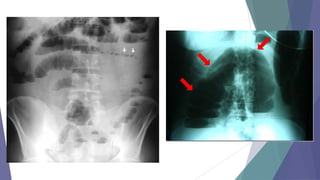

Radiografía simple de abdomen

niveles

hidroaéreos

abdomen agudo

distensión de

asas intestinales

datos de

irritación

peritoneal (íleon)

Delimitar siempre la sombra de los órganos

descritos y además los músculos psoas, el

contorno de la vejiga, la columna vertebral y la

pelvis.

Presencia de

abscesos

•TRES

PROYECCIONES

Decúbito supino.

Bipedestación.

Decúbitos laterales.

•IMÁGENES:

1. Ileo (distensión de

asas, niveles H-A).

2. Neumoperitoneo.

3. Calcificaciones (litiasis

biliar, renal, pancreática).

ESTUDIOS PARACLINICOS presencia del líquido intraabdominal  Radiografíasimple de abdomen niveles hidroaéreos abdomen agudo distensión de asas intestinales datos de irritación peritoneal (íleon) Delimitar siempre la sombra de los órganos descritos y además los músculos psoas, el contorno de la vejiga, la columna vertebral y la pelvis. Presencia de abscesos •TRES PROYECCIONES Decúbito supino. Bipedestación. Decúbitos laterales. •IMÁGENES: 1. Ileo (distensión de asas, niveles H-A). 2. Neumoperitoneo. 3. Calcificaciones (litiasis biliar, renal, pancreática).